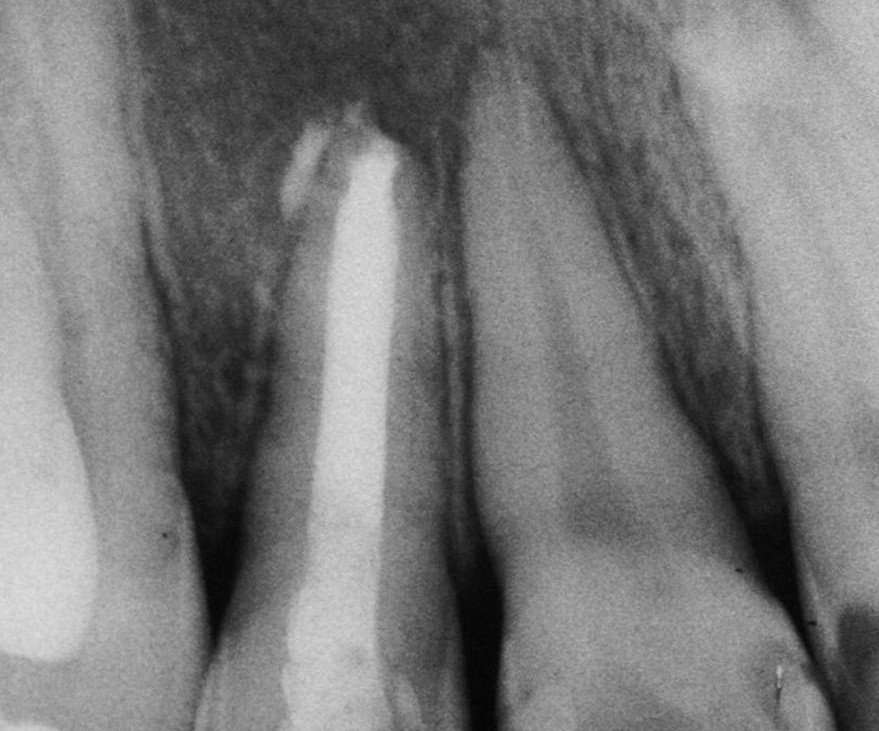

O paciente do gênero masculino, 15 anos, apresentou-se abaulamento na região anterior direita do palato, sem qualquer sintoma. O teste de sensibilidade pulpar realizado no dente 12 apresentou resposta negativa e o teste de percussão vertical, resposta positiva. Ao exame radiográfico observou-se lesão periapical se estendendo à distal do dente 12:

Estabelecido o diagnóstico clínico de cisto periapical iniciou-se o tratamento endodôntico. Foi realizado acesso coronário e preparo químico-mecânico com limas manuais utilizando como substância irrigadora o hipoclorito de sódio à 2,5%.